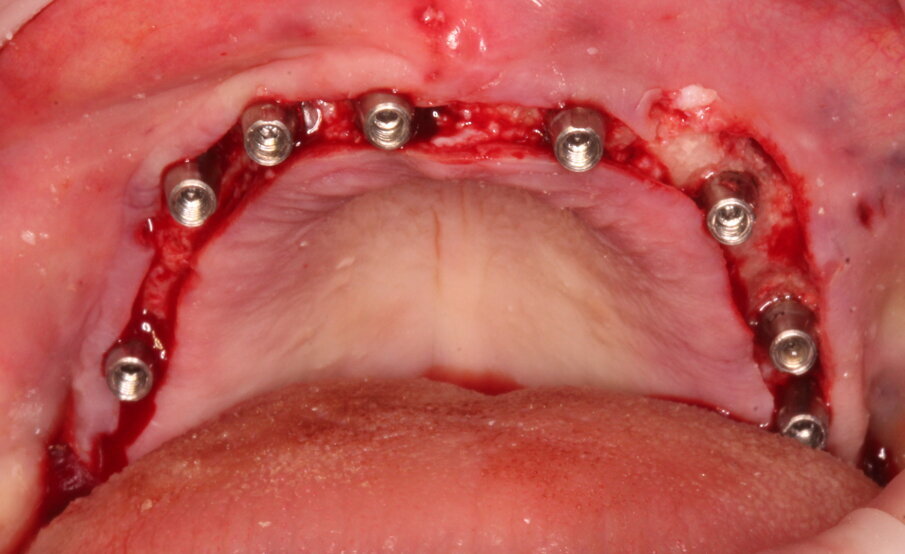

Gli impianti vengono distribuiti lungo tutta l’arcata cercando il parallelismo e limitando il più possibile i cantilever (6-7 impianti superiori e 5-6 impianti inferiori). La scelta di utilizzare i monconi dritti (grazie al parallelismo degli impianti) è da preferire in quanto quest’ultimi sono anche i più robusti e resistenti nel tempo al carico assiale; inoltre caricano l’impianto lungo il suo asse limitando i carichi disassati. Una volta elevato il lembo mucoperiosteo ed evidenziato l’osso alveolare o basale, attenzione deve essere fatta nel fare un’ostectomia riduttiva mediante una fresa a palla del diametro di 0,6-0,8 cm per creare un piano più uniforme possibile tale da formare una piattaforma d’osso alla stessa altezza, guadagnando anche spessore V-L ed uniformità. Gli impianti devono essere posizionati alla stessa altezza tra di loro e distanziati in maniera tale da favorire le manovre di igiene orale inter-implantare. Una volta posizionate le fixture sottocrestali (1-3 mm) come descritto, vanno connessi i monconi solitamente con collare mucoso di 3-4,5 mm in altezza, ponendo particolare attenzione che i tessuti molli suturati non coprano la parte di accoppiamento conometrico. Verificato il parallelismo corretto dei monconi mediante i pin parallelizzatori, siamo certi che l’accoppiamento e la disconnessione delle cappette contenute nella protesi potrà avvenire nel miglior modo possibile senza creare tensioni.

Un’impronta in silicone o digitale sulle cappette in situ accoppiate va presa alla fine della chirurgia, una volta suturati i lembi. Il paziente lascia lo studio con delle cappette provvisorie in Peek a protezione dei monconi e con la sua protesi riadattata oppure con una stampata del Brega riempita con impacco parodontale come medicamento.